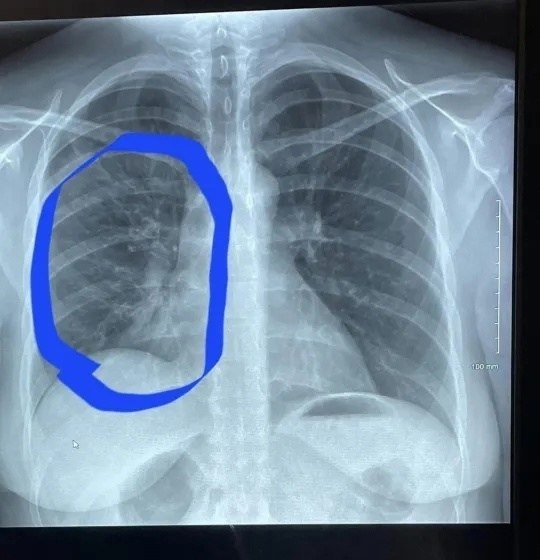

Вейпинг привёл лёгкие 30-летней женщины в состояние, характерное для 80-летних курильщиков.

Женщина использовала вейп на протяжении чуть более трёх лет, находя этот процесс весьма приятным. Однако однажды она заметила "хлопающий" звук при дыхании и испытала резкую боль.

В больнице ей поставили диагноз пневмония и сообщили, что её лёгкие выглядят как у пожилого человека, курившего на протяжении десятилетий.